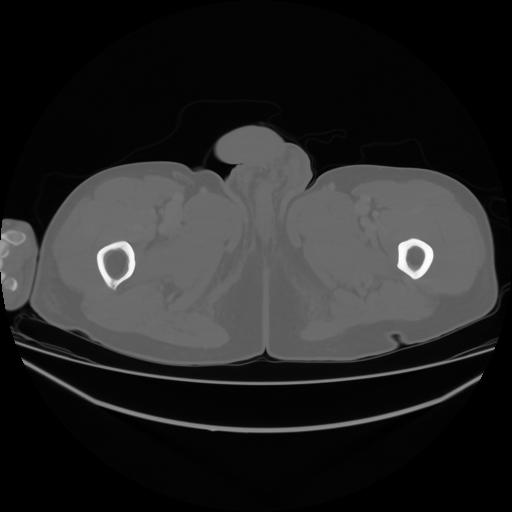

4 CUERPO,CE,Axial,3.0,CUERPO,,